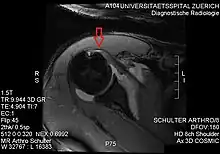

Imaging

There is no singularly imaging device or technique for a satisfying and complete subscapularis examination, but rather the combination of the sagittal oblique MRI / short-axis US and axial MRI / long-axis US planes seems to generate useful results. Additionally, lesser tuberosity bony changes have been associated with subscapularis tendon tears. Findings with cysts seem to be more specific and combined findings with cortical irregularities more sensitive.[5]

Since the long biceps tendon absents itself from the shoulder joint through the rotator cuff interval, it is easily possible to distinguish between the supraspinatus and the subscapularis tendon. Those two tendons build the interval sling.